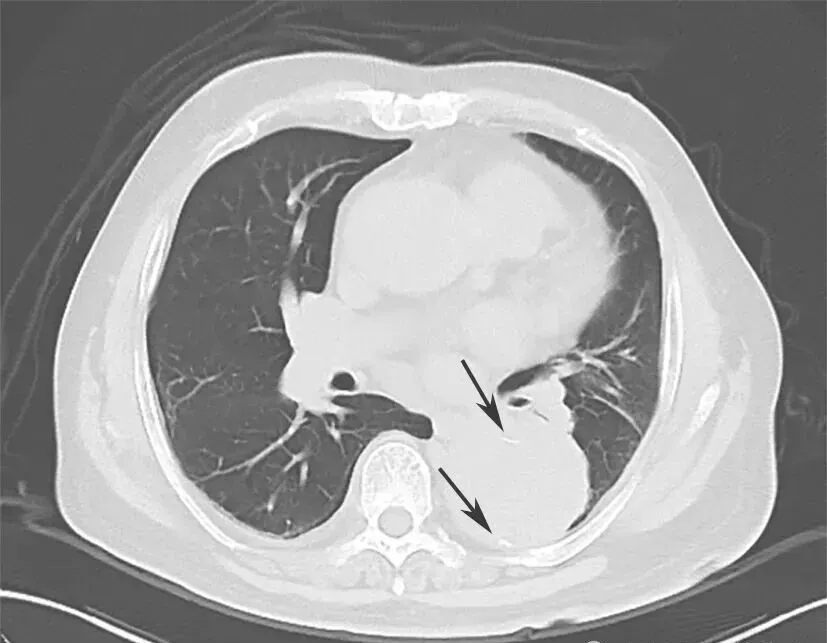

4.肺CT平扫

降主动脉瘤样扩张,直径较前有所增加,可见内膜移位,不除外主动脉夹层(图1)。

图1 肺部CT平扫(箭头处钙化点内移)

3.患者既往存在升主动脉瘤样扩张病史多年,此次复查肺CT显示升主动脉直径较前有所扩大。症状上呈撕裂样疼痛,加之D-二聚体显著升高,考虑患者主动脉夹层的诊断可能性大。

对于急性胸痛的患者,2010年AHA指南中提出疑诊主动脉夹层(aortic dissection,AD)的高危易感因素、胸痛特征和体征。IRAD研究基于上述高危因素提出AD危险评分,根据患者符合危险因素分类(高危易感因素、高危疼痛特征及高危体征)的类别数计0~3分(0分为低危,1分为中危,≥2分为高危);该评分≥1分,诊断AD的敏感度达95.7%。因此,对存在上述高危病史、症状及体征的初诊患者,应考虑AD可能并安排合理的辅助检查以明确诊断。基于患者入院时病史询问、体格检查对疾病确诊极为重要。本例患者既往有升主动脉瘤样扩张及高血压病史多年,因突发胸痛入院,AD危险评分≥2分,为AD高危,且门诊胸部CT平扫可见降主动脉瘤样扩张,直径较前有所增加,可见内膜移位,高度怀疑主动脉夹层。